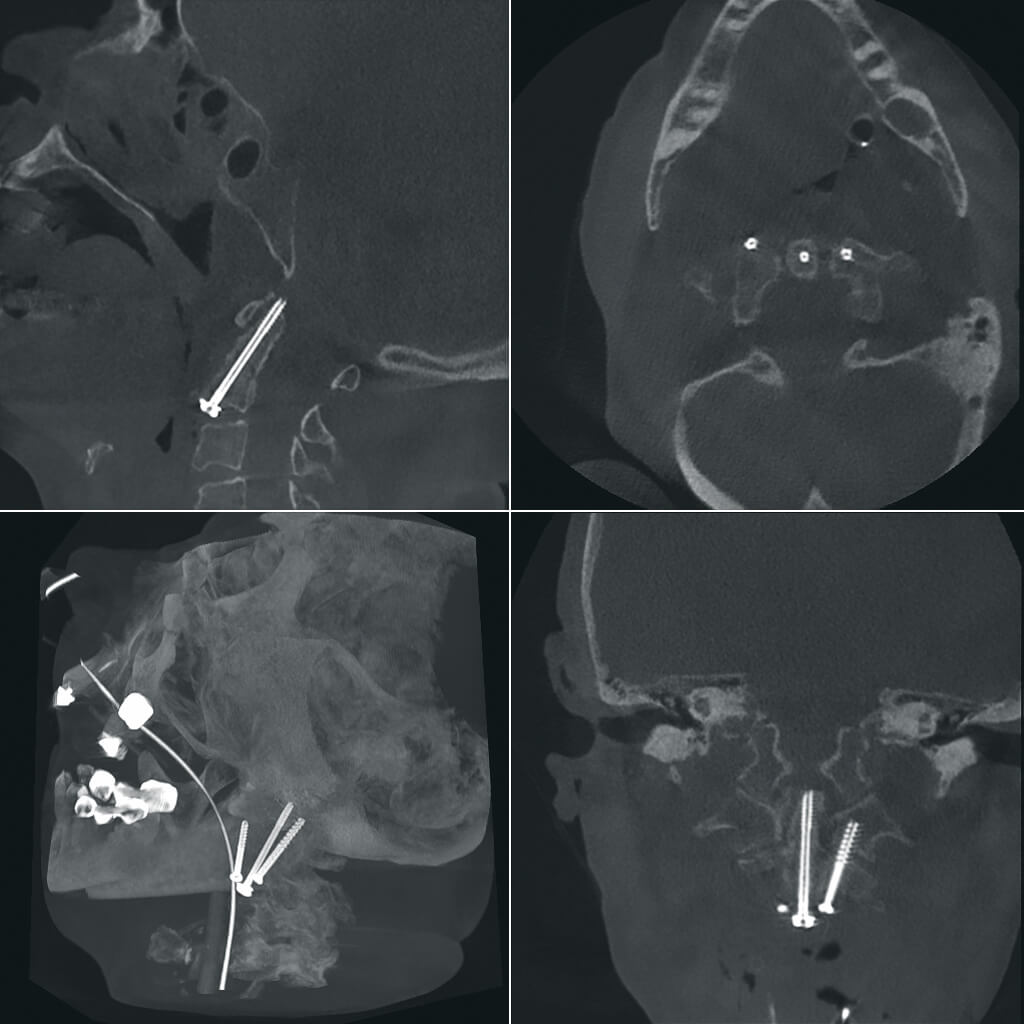

Просмотр и обработка 3D изображений непосредственно в операционной

В ходе проведения рентгенохирургических вмешательств хирург имеет возможность на референтном мониторе рабочей станции осуществлять просмотр и обработку только что полученных 3D изображений, выполнять реконструкцию полученных данных для получения объемных изображений различного разрешения и размера поля, проводить измерения в ортогональных проекциях, выбирать оптимальный угол доступа.

Высокая детализация для сложных операций

Полное отсутствие искажений снимков в сочетании с высоким динамическим диапазоном широко востребованы как при сложных операциях в нейрохирургии, сосудистой хирургии, инвазивной радиологии, так и в гибридных областях применения, а также в ортопедии, травматологии. В сосудистой хирургии особенно важны высокий динамический диапазон и пространственное разрешение, обеспечивающие детальную визуализацию даже мельчайших сосудов. Специализированное программное обеспечение SmartVascular позволяет проводить настройку системы для васкулярных операций и сосудистой хирургии.

Точная визуализация анатомических деталей, мягких тканей и костных структур обеспечивается за счет светочувствительной матрицы 3kх3k пикселей с высоким динамическим диапазоном.